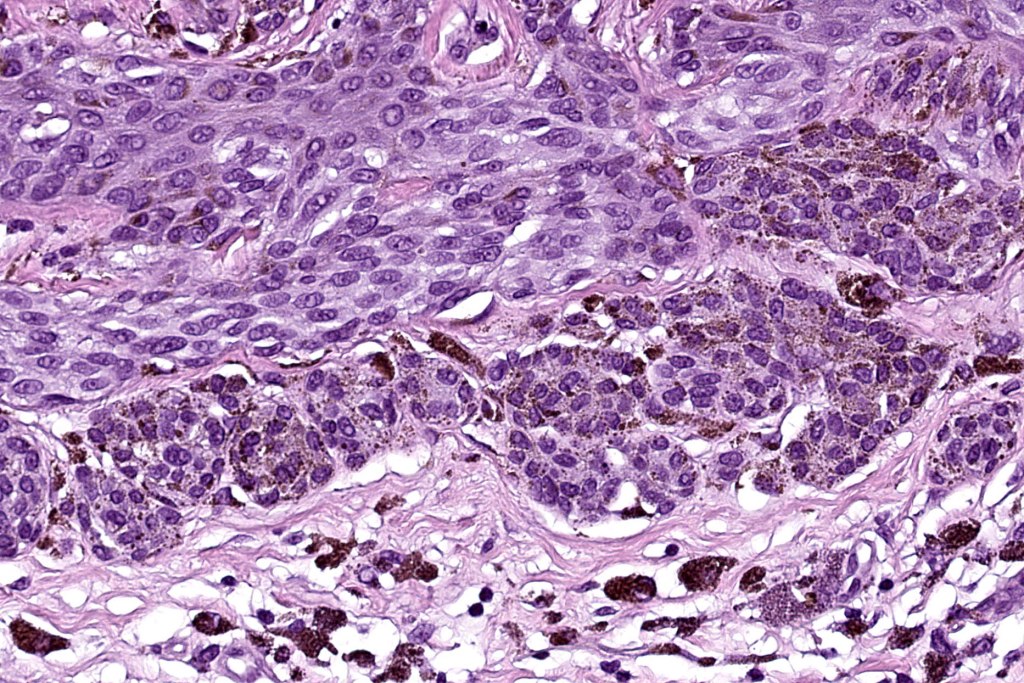

•Variant of Spitz nevus, readily identifiable at scanning magnification in the majority of cases

•Vertically orientated oval junctional nests

. Heavy pigmentation although hypopigmented/amelanotic varinats can be encountered

•Spindle cells with small nucleoli

•Mild pleomorphism

•Kamino bodies

•80 % kinase fusions (NTRK3-58%), HMB45 diminishes with depth in compound lesions